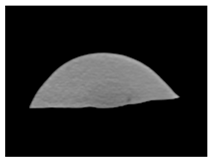

| MRI–T1 |  |  |  |

| MRI–T1 |  |  |  |

| MRI–T1 |  |  |  |

| MRI–T1 |  |  |  |

| MRI–T1 |  |  |  |

| MRI–T1 |  |  |  |